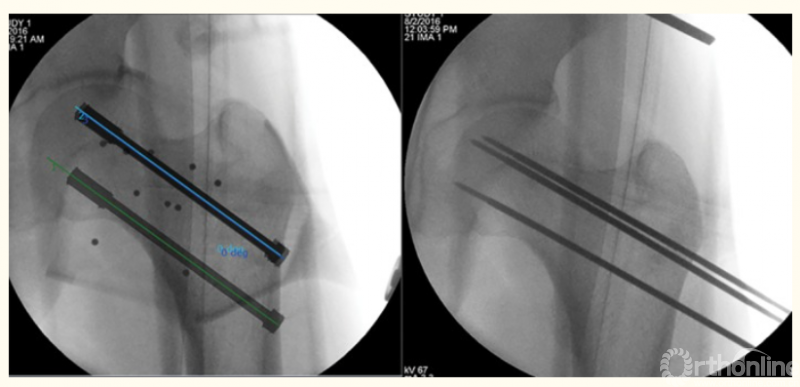

3、股骨颈骨折的机器人辅助手术